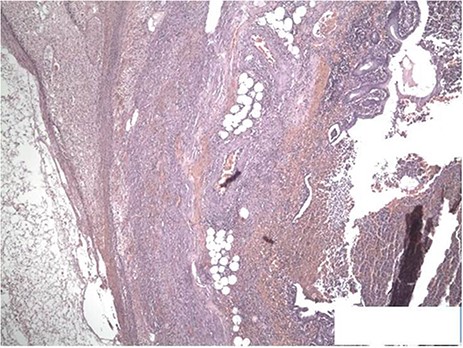

The surgical specimen received was the cecal appendix with an ovoid shape and measures of 6.5 × 4 × 3 cm. On sectioning, the appendix was 1.2 cm in diameter with a wall thickness of 0.4 cm with a sanguineous secretion inside surrounded by edematous soft tissue and vascular congestion. The section showed the cecal appendix with architectural distortion due to the acute inflammatory infiltrate with neutrophils and eosinophils that destroyed the mucinous secretory epithelium in patches and infiltrated the muscle wall and the adjacent soft tissues forming microabscesses (Figs 4 and 5). The pathology department reported acute appendicitis with microabscesses. The patient was discharged 48 hours after surgery without complications.

The sections show the appendiceal wall from mucosa to serosa with transmural inflammation. Focal mucosal ulceration is seen as well as congested vessels. Crypt architecture is preserved. H&E ×40.